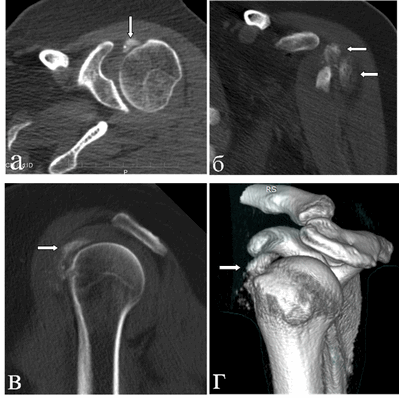

При компьютерной томографии выявлена диффузно-глыбчатая оссификация капсулы сустава по медиальной поверхности (на 8-12 часах условного циферблата головки плечевой кости по сагиттальным снимкам) на участке размерами 1,5х0,7х4,5 см плотностью от 200 до 890 HU (средней плотностью ~ 300 HU), медиальных отделов субдельтовидной сумки, в зоне малого бугорка (в области фиксации сухожилия подлопаточной мышцы), более «нежная» по капсуле вокруг вертикального сегмента сухожилия длинной головки бицепса; отсутствует в области фиксации остальных сухожилий ротаторной манжеты к большому бугорку и в самом сухожилии длинной головки бицепса (рис. 3). Данный характер оссификации также подтверждает представления о фазном характере течения рассматриваемой патологии.

Рис. 3. КТ левого плечевого сустава пациентки Л., 50 лет (март 2019 г.). Аксиальный срез (а) на уровне верхней части головки плечевой кости: бобовидной формы крупный кальцинат по медиальному контуру головки плечевой кости в зоне расположения капсулы; МПР-корональный срез демонстрирует расположение кальцинатов по капсуле вдоль вертикального сегмента сухожилия длинной головки бицепса (б), МПР-сагиттальный срез весьма наглядно показывает локализацию кальцинатов по капсуле и в зоне субдельтовидной сумки (в) и 3D реконструкция правого плечевого сустава в объемном представлении детализирует патологическое состояние в мягкотканых структурах сустава (г). Визуализируется оссификация капсулы вокруг сухожилия бицепса; кальцинаты в подклювовидном и субдельтовидном пространствах

Таким образом, МР-исследования с интервалом более одного года у пациентки Л. позволили наблюдать миграцию крупного кальцината в периартикулярных тканях плеча, выявить периартикулярные мягкотканые изменения сухожилий, капсулы сустава. При этом мультиспиральная компьютерная томография позволила более отчетливо визуализировать кальцификаты, точно оценив их анатомическую принадлежность (по капсуле, вне полости сустава), распространенность и плотностные характеристики.